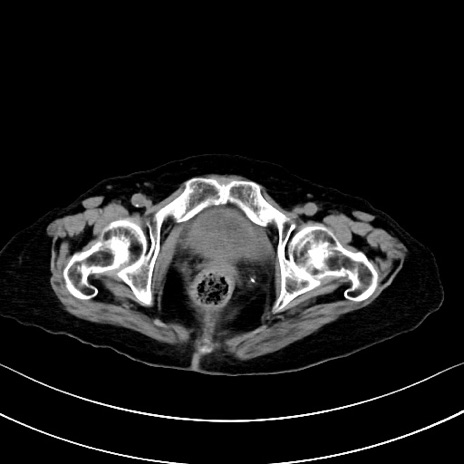

横断像

他院CT